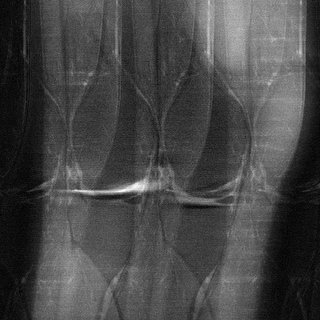

MRI

This is a low quality image of a knee created by running an MRI machine faster than usual and interpreting that raw data the traditional way, without AI. NYU School of Medicine / Facebook